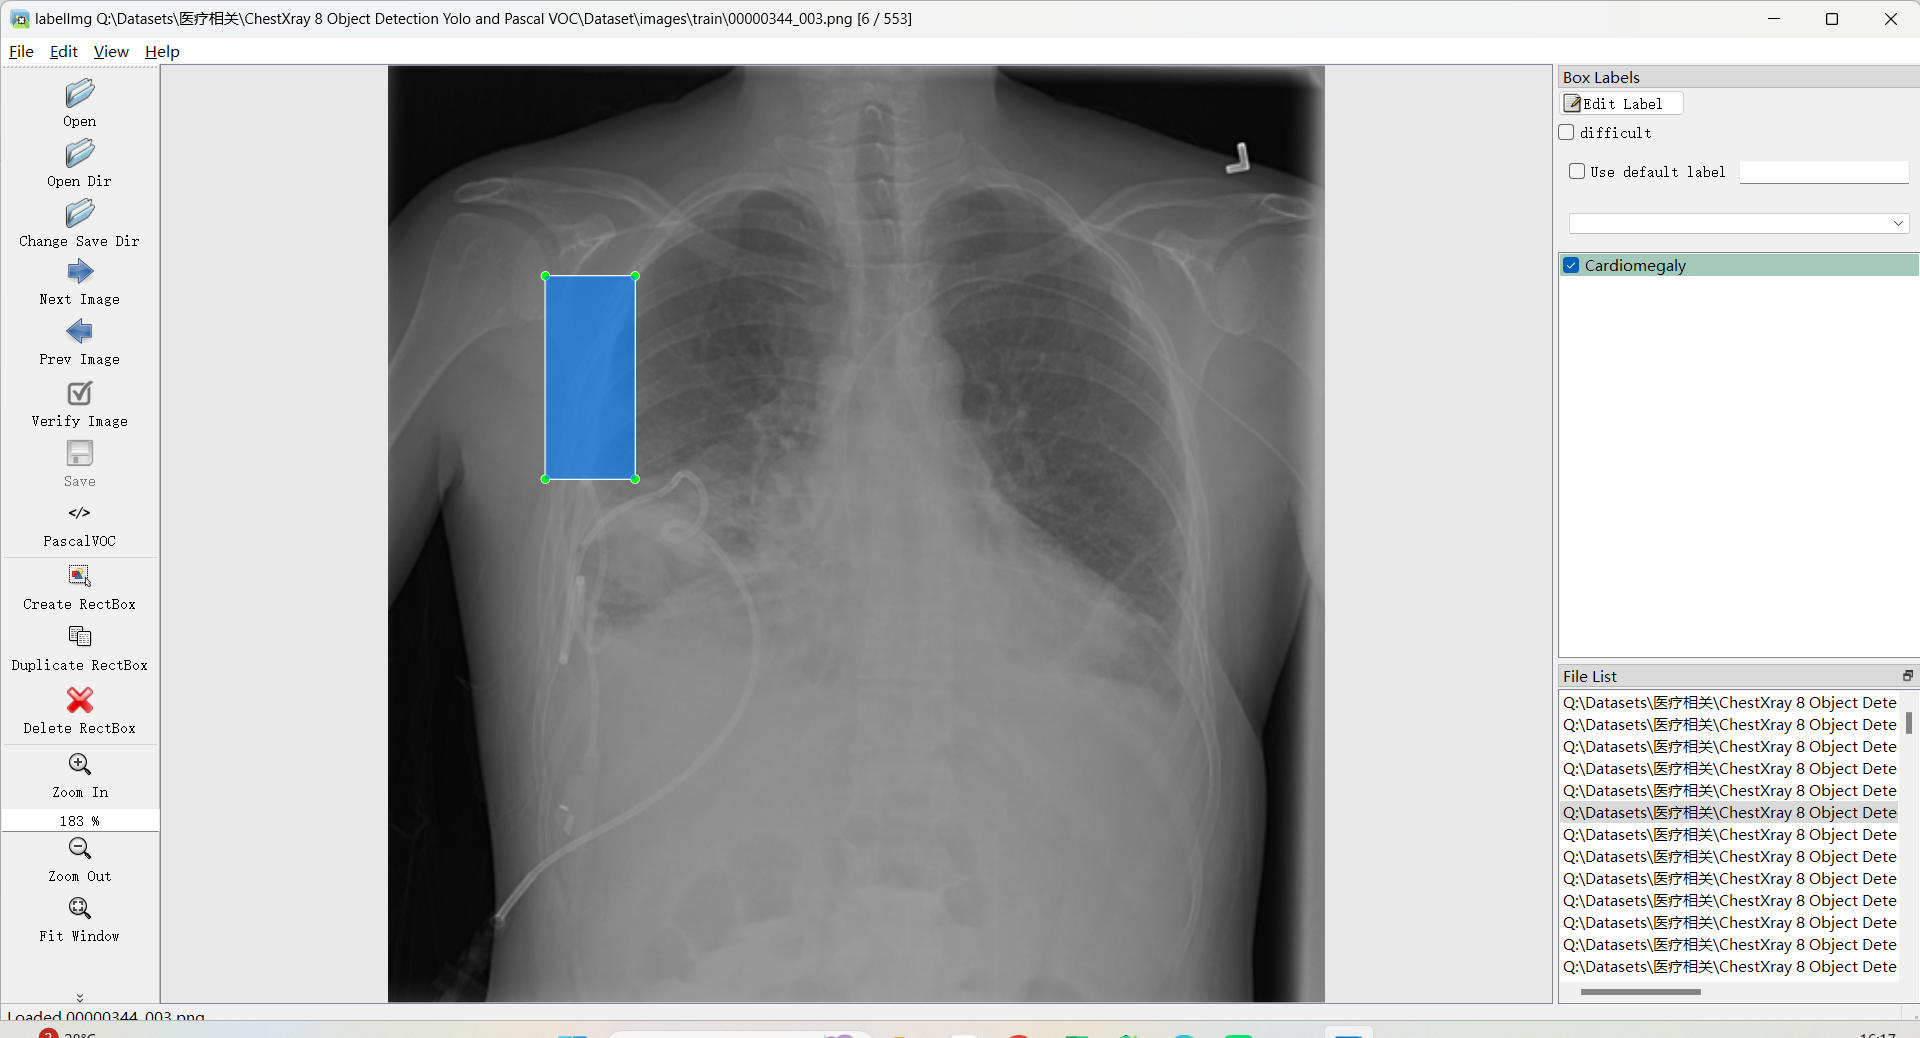

标注类别名称: Infiltrate:浸润影;Atelectasis:肺不张;Cardiomegaly:心脏肥大;Nodule:结节;Effusion:积液(胸腔积液)

使用标注工具:labelImg

标注规则:对类别进行画水平矩形框

标注示例: